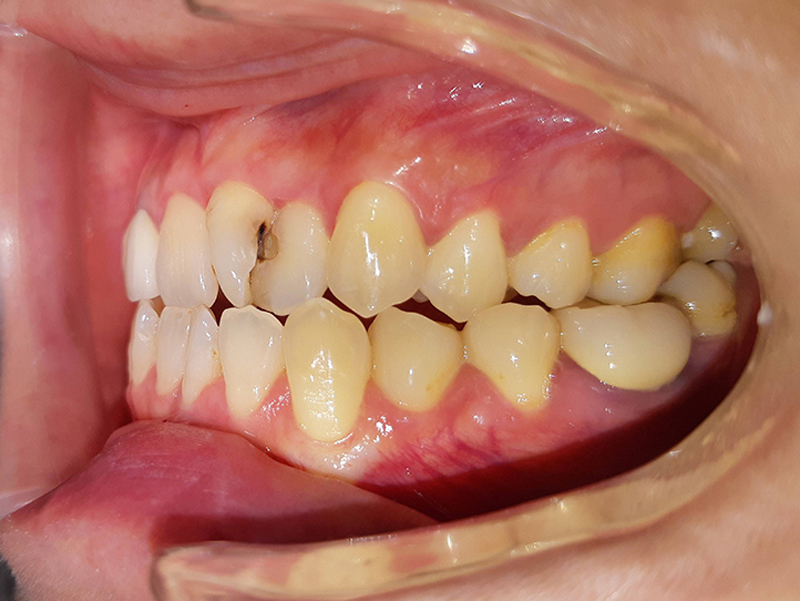

案例:不開刀齒性戽斗前後比較